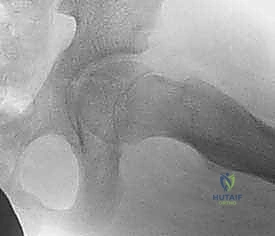

ج. تشوه الورك للداخل (Coxa Vara)

يحدث عندما يلتئم الكسر بزاوية غير طبيعية (زاوية عنق الفخذ تصبح أقل من الطبيعي). يؤدي ذلك إلى عرج دائم أثناء المشي. التثبيت الجراحي القوي والمحكم هو الحل الأمثل لمنع هذا التشوه.

- العودة للحياة الطبيعية: بعد التأكد من الالتئام التام (عادة بعد 3 إلى 6 أشهر)، يمكن للطفل العودة للأنشطة المدرسية واللعب، مع تجنب الرياضات العنيفة لمدة عام على الأقل.